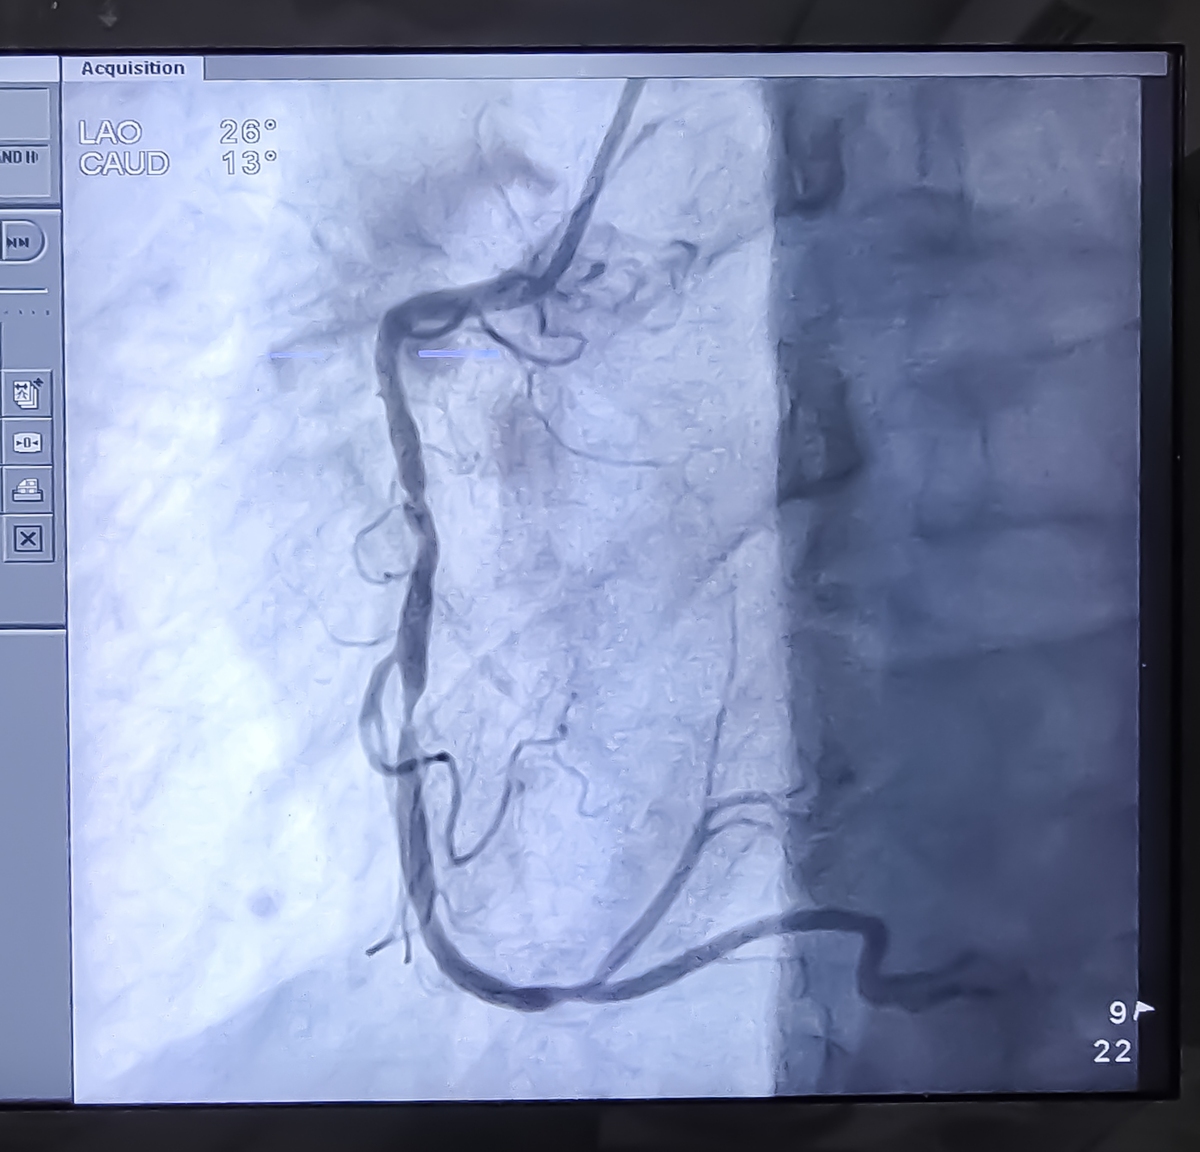

颈动脉斑块破裂形成的溃疡和漂浮血栓:超声造影和CTA/DSA证实

超声造影检查后证实颈动脉斑块破裂形成了溃疡和漂浮血栓。后续的CTA和DSA检查也证实了漂浮血栓的存在。